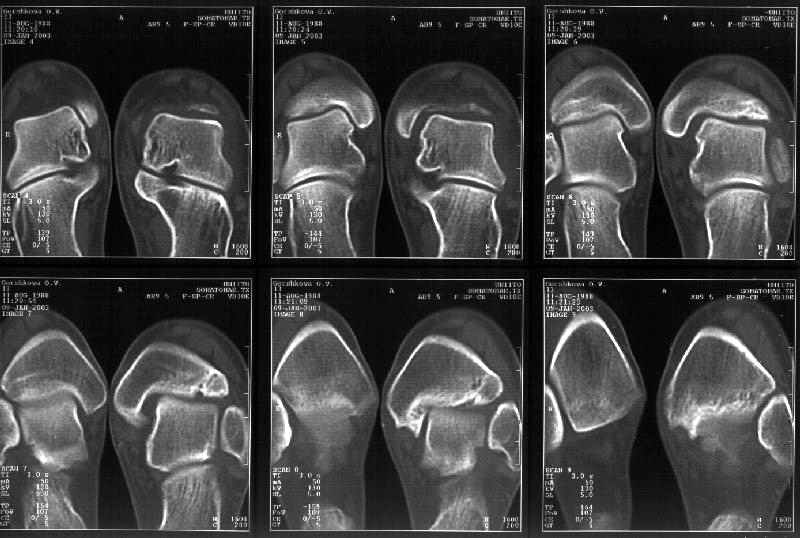

Здесь 4 среза, начиная от основания лодыжки и проксимальнее. Где, по Вашему мнению, проходит линия перелома, отделяющая переднюю часть внутренней лодыжки от большеберцовой кости? Заранее спасибо.

Кликните для загрузки файла get_image.jpg

38KB (39385 bytes)

Я пометил линию перелома черной линией.

К сожалению на последних присланных срезах КТ нет более низкого, через таран, среза, который был на прежнем майле. На XR я попытался показать

стержень внутри сустава и то как он раскрывает пространство между тараном и мед. малеолом.